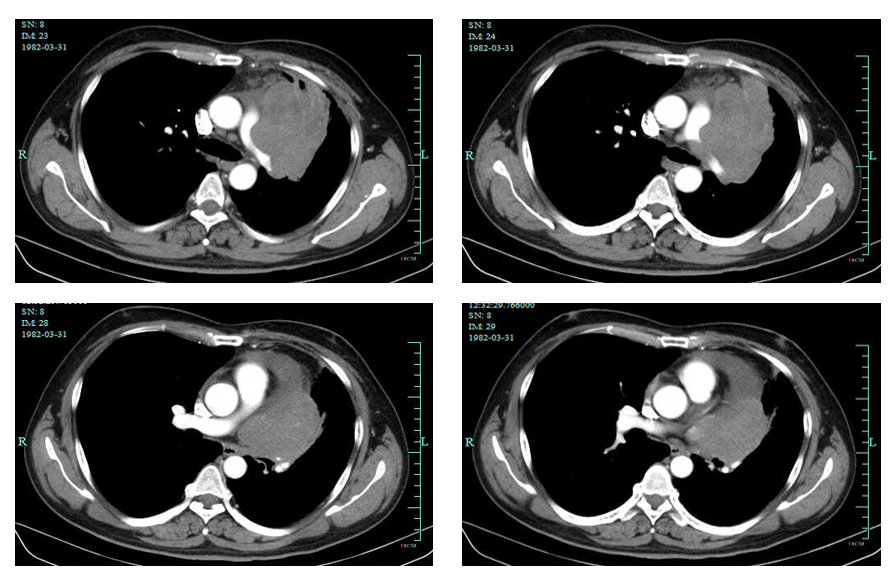

2022-10-06胸部增强CT:对照2022-07-31CT病灶明显缩小;纵隔及邻近多发血管受侵,较前明显好转,心包积液,较前减少。

影像学检查图像(基线、2周期后、6周期后原发灶变化)